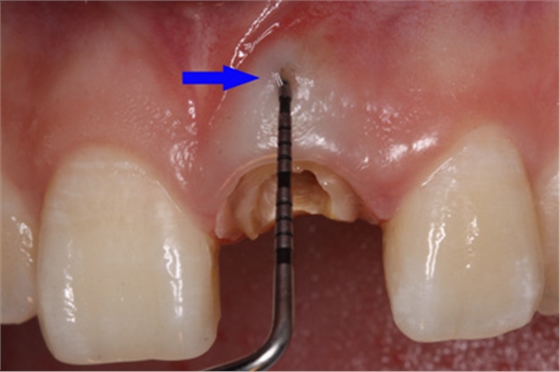

因此,臨床上正確判斷穿孔的發(fā)生十分必要。穿孔出現(xiàn)的主要表現(xiàn)為:拔凈牙髓后,根管內(nèi)出血明顯,吸潮紙尖中部有血跡,尖端干凈;x線診斷絲從根管壁穿出;根管長(zhǎng)度測(cè)量?jī)x在根管銼未到工作長(zhǎng)度時(shí)顯示超出根尖孔;顯微鏡下能看到明顯的穿孔部位和牙周軟組織的粉紅顏色,或陳舊的壞死樣軟組織。

唇側(cè)出現(xiàn)瘺管